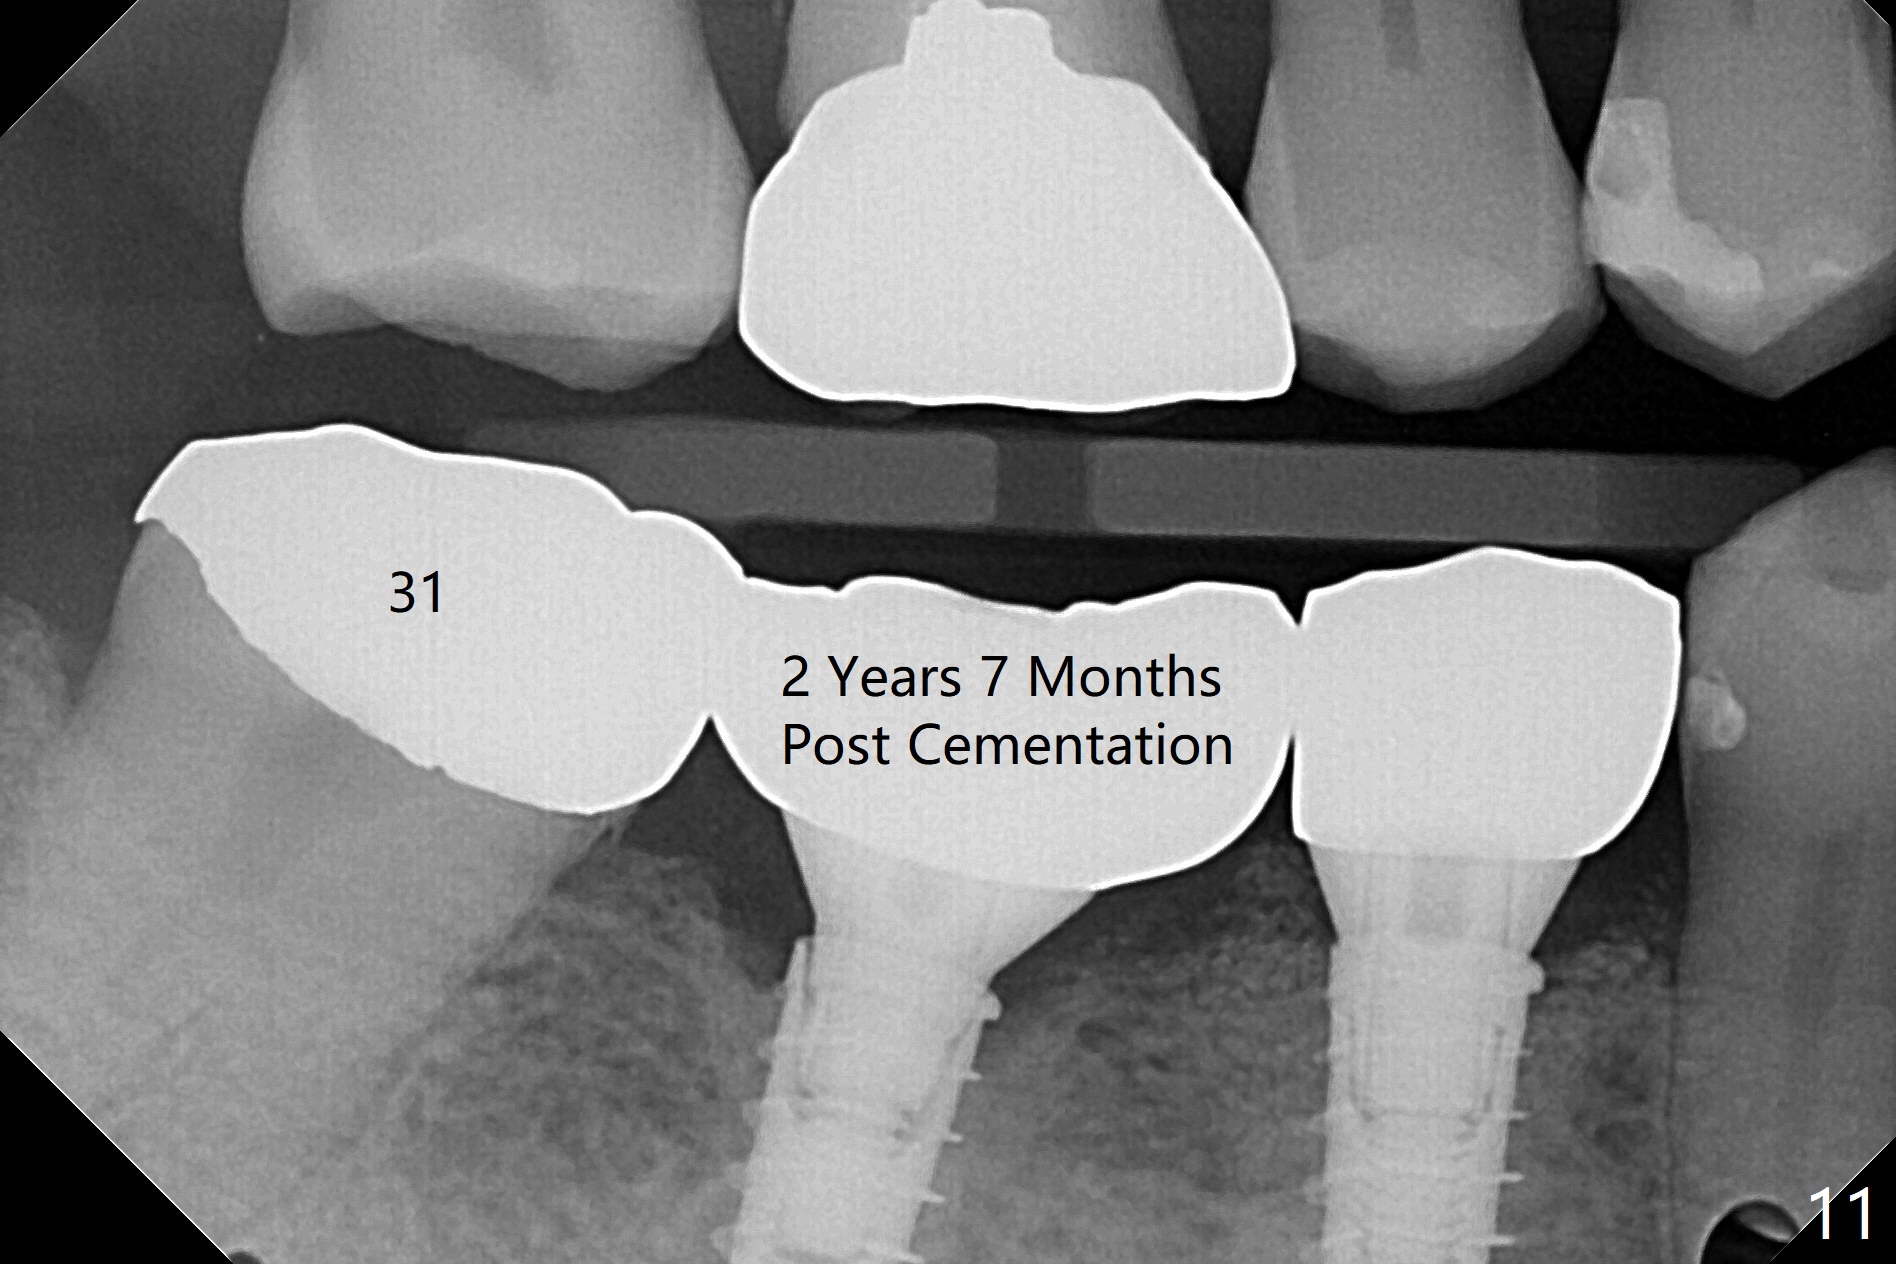

After incision, the ridge at #29 and 30 is found ~ 5 mm wide buccolingually. To place a 4x11 mm IBS implant at #30, the ridge is expanded using BEB technique (bone expansion and bending, Fig.1). It appears that the initial osteotomy at #29 is mesial (Fig.1 yellow dashed line: the distal surface of the root of the tooth #28). After moving the osteotomy distal, the final implant position at #29 (4x11 mm) is within normal limit (Fig.2). The bone at #29 seems to be not so dense that bending (using 1.6 mm drill) is not necessary (using Magic Split and Magic Expanders 3 and 3.8 mm). Later the implant at #30 (4x11 mm) is placed deeper (Fig.3). After placing bone graft around the implants/abutments and suturing, the ridge looks wider with apparent formation of the gingival bands around the abutments (Fig.4 *). Three months and a half postop, bone loss is minimal (Fig.5) and gingival bands forms around the abutments (Fig.6). Fig.7 is taken 1 month post cementation (panoramic X-ray). The patient chews normally 1 year (Fig.8) and nearly 2 years (Fig.9,10) post cementation. The crown at #31 needs recementation 2 years 7 months post #30 cementation; the incomplete seating of the abutment was noted for the first time (Fig.11). Five months later the patient is going to be retired and wants to travel abroad. After approval, the access hole was reopened; articulating paper shows under occlusion of the crown (Fig.12). Since the gap between the abutment and the implant is large, the abutment/crown complex seems to be necessary to be turned (Fig.13 curved arrow). The proximal surfaces of the crown need to be trimmed (straight lines). After turning, the crown sits down with screw tightening; the patient feels pain from the gingival cuff (Fig.14). After turning, the abutment appears to be completely seated (Fig.15). In fact the mesial and distal surfaces of the crown should have clearance from the neighboring teeth (Fig.14) so that pick-up impression is able to hold the crown/abutment complex securely (Fig.16: *). The crown is separated from the abutment after crown repair. They are seated together (loose connection) using the crown as a guide to seat the abutment. BW is taken without the crown. It appears that the abutment remains seated completely (Fig.17). The apical space is equal between #29 and 30 (Fig.17, as compared to Fig.5).